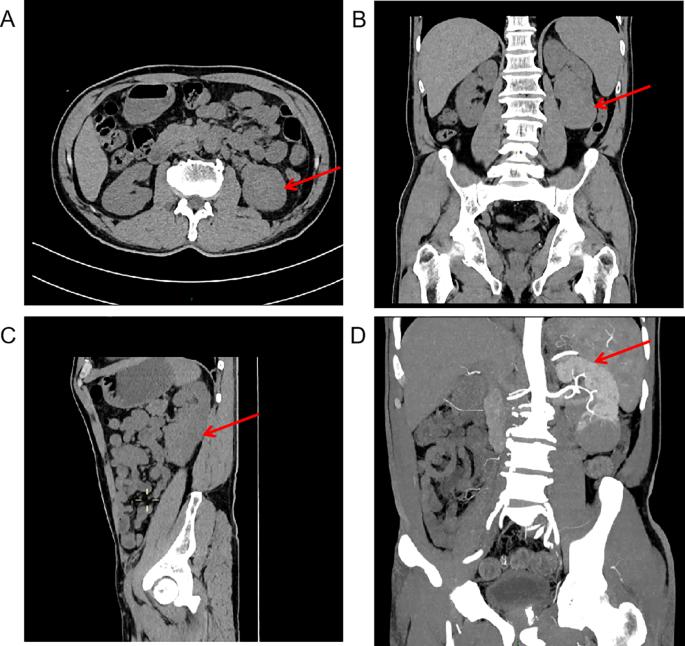

血小板特异性抗体检测显示抗GMP140抗体阳性。骨髓吸出物显示红系、粒细胞和单核细胞谱系正常,同时巨核细胞成熟受损(每个低倍视野21个巨核细胞,仅包括1个血小板生成形式),没有母细胞白血病、骨髓纤维化或淋巴瘤浸润,有助于排除骨髓增生性肿瘤(MPN)和骨髓增生异常综合征(MDS)。同时进行的外周血分析证实了明显的血小板减少症,其特征是血小板稀少、分散,其他谱系没有发育不良。计算机断层扫描(CT)和CT血管造影确定了8.7×5.6×3.0 cm浸润性左肾肿块桥接肾窦和下极,表现为实质和血管浸润(图1A-D)。肾脏动态闪烁扫描显示,尽管左肾形状不规则,但两个肾脏的血流灌注和肾小球滤过功能正常(图2)。

图1 肾肿瘤的计算机断层扫描和肾动脉造影。(A)腹部CT平扫显示左肾软组织肿块,箭头为红色。(B)冠状位CT平扫显示肿块位于左肾窦和左肾下极,如红色箭头所示。(C)矢状CT平扫显示,肿块位于左肾窦和左肾下极,如红色箭头所示。(D)肾动脉计算机断层扫描血管造影扫描描绘了左肾动脉与位于左肾窦和下极的软组织肿块相邻并沿其穿过,由红色箭头标记